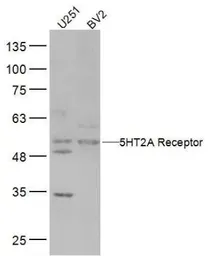

5-HT2A receptor antibody

Cat. No. GTX37799

ApplicationsWB IHC-P IHC-Fr FCM

ReactivityHuman, Mouse, Rat